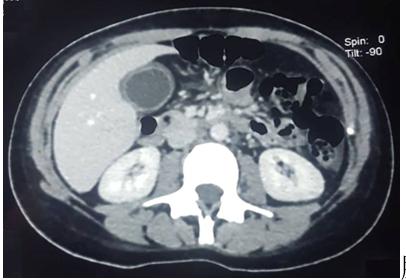

此外,患者的胸片正常。腹部超声显示胆囊壁厚12 mm,胆囊壁回声不均,但胆囊体积不大,其内未见结石。肝内外胆管未见扩张,有少量腹腔积液。

超声可能看不清结石,或者结石太小?然而,患者进一步接受腹部CT,结果显示胆囊壁增厚、胆囊体积增大,伴肝肿大,密度均匀。由此可见,急性胆囊炎毋庸置疑,但CT依然未发现结石!